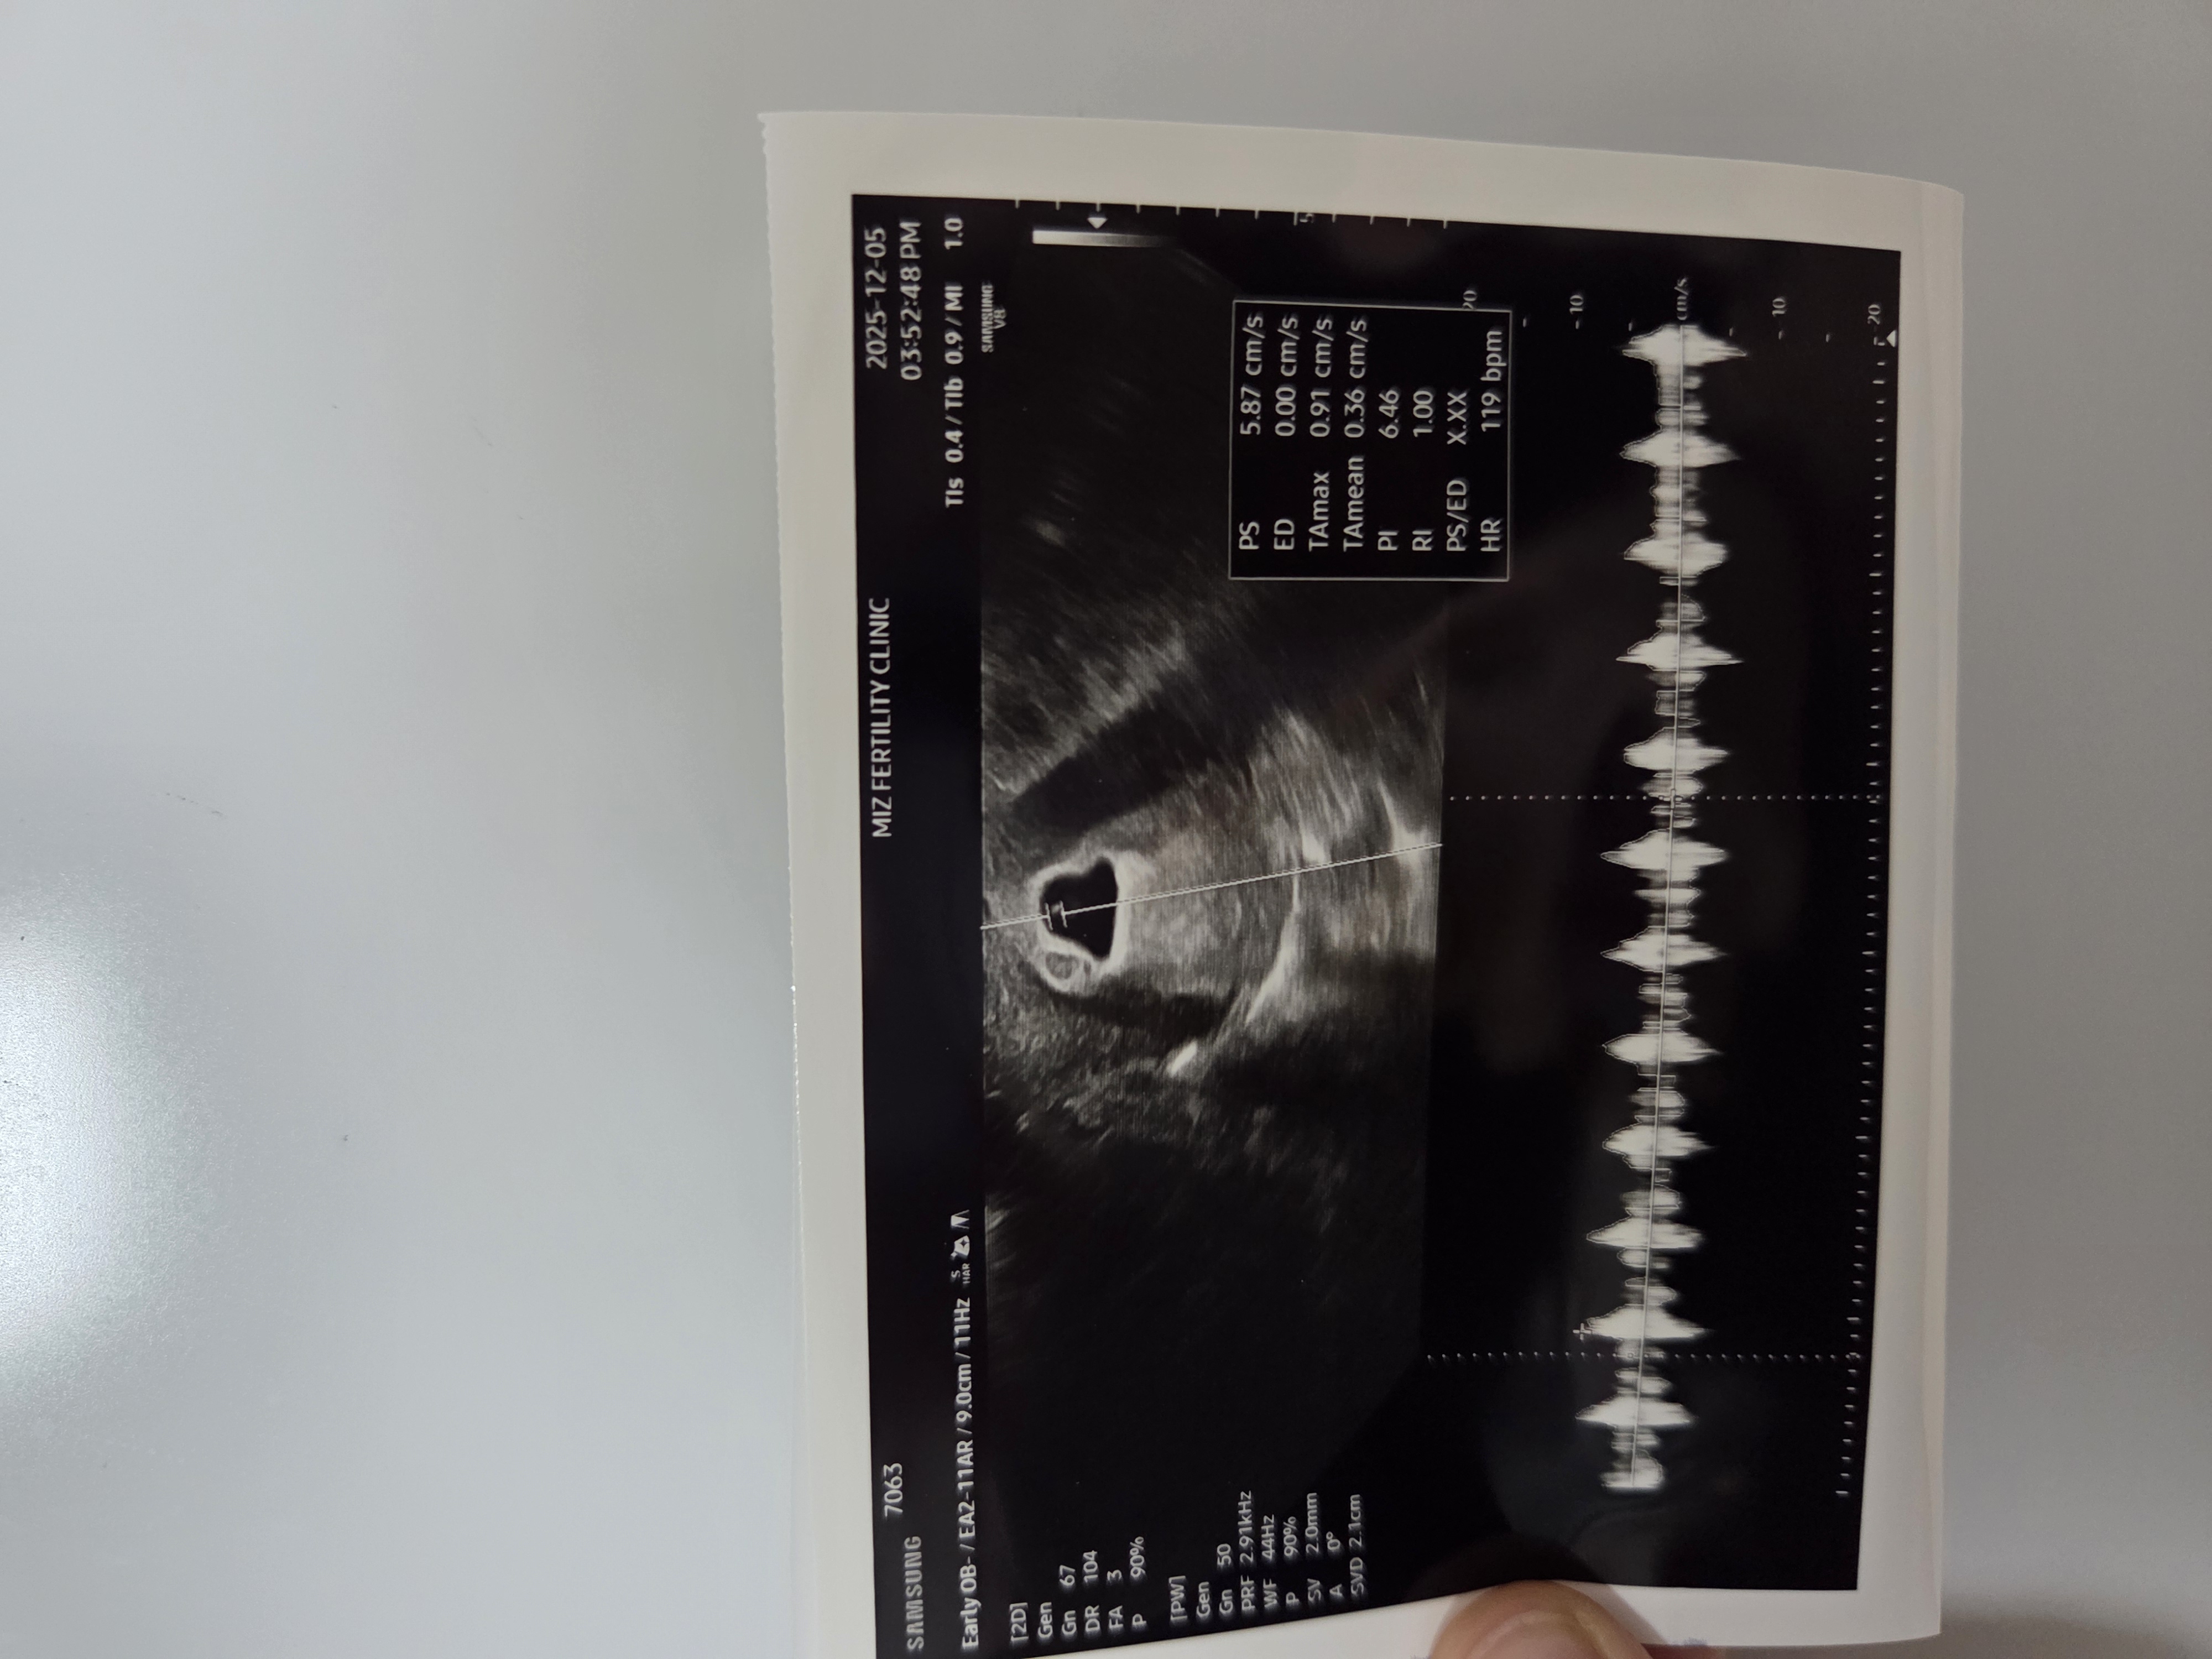

5주6일 심장소리 듣고왔어요~

난황이 조금 크다해서 걱정되긴하지만 그래도 심장소리는 정상이라고해서 마음편히 있으려구요😁